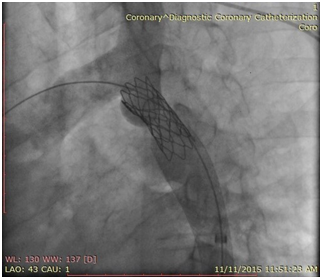

The patient was brought to the endovascular suite and the right groin was prepped. Moderate conscious sedation was administered during the case via a peripheral IV. Access was gained into the right common femoral artery and a 6 French sheath was placed. A pigtail catheter was then placed in the mid descending thoracic aorta and an angiogram was performed demonstrating severe narrowing of the thoracic aorta. The left subclavian artery was not visualized, multiple collateral vessels were seen arising from the mid thoracic aorta. Initial attempts at crossing the stenotic segment with a glide wire and cobra catheter were unsuccessful. The left arm was then prepped and access was gained into the left brachial artery and a 5 Fr sheath was placed. A pigtail catheter was then advanced into the aortic arch and an arch aortogram was performed demonstrating normal branching anatomy with delayed filling of the distal thoracic aorta noted. Simultaneous pressure measurements proximal and distal to the stenosis demonstrated a gradient of 40mmHg. After repeated attempts the stenosis was finally crossed from below using a glide wire and cobra catheter. The glide wire was then exchanged for a 260cm Double Curved Lunderquist wire (Cook Medical). The stenotic segment was predilated with an 8mm by 4cm balloon with resolution of the tight waist seen at 10 atm. The 6 French right groin sheath was then upsized to a 11 Fr sheath. A 20mm diameter by 55mm long Wallstent (Boston Scientific) was then placed across the stenotic segment with the proximal end of the stent positioned just at the origin of the left subclavian artery and the distal end within the descending thoracic aorta past the focal stenotic area. As the stent was unsheathed it migrated distally and opened up distal to the stenotic segment. A 3.9cm long covered balloon expandable Cheatham-platinum (CP) stent (NuMed Inc) was then selected and hand crimped on a 16mm by 6cm long Z-MED (NuMed Inc) balloon. The existing short 11 Fr sheath was replaced for a 70 cm long 11 Fr Mullens sheath which was advanced past the stenotic segment. The balloon mounted stent was then accurately positioned once again, taking care not to cover the left subclavian artery. The sheath was pulled back repeat angiogram performed from the left subclavian artery catheter, and the balloon was carefully inflated. The balloon was deflated and removed. Completion angiogram from the arm approach demonstrated accurate placement of the stent with significant improvement in luminal diameter noted. Repeat simultaneous pressure measurements across the stent demonstrated no residual gradient. The patient was then transferred to the recovery bay were the sheath was removed once the ACT was below 170. The patient had an uneventful post-op recovery and was discharged the following day. At one week clinical follow up, the patient reported significant improvement in symptoms (Figures 1‒4).

Figure 4 Completion angiogram demonstrated accurate placement of the stent with significant improvement in the luminal diameter.